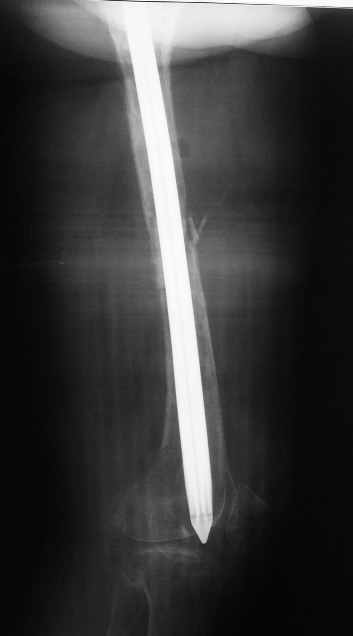

По просьбе коллег выношу на обсуждение следущий случай лечения перелома бедра, о дальнейшем лечении больной 48 лет с РПА. Анамнез: В 2005 году в ЦРБ - остеосинтез перелома бедра пластиной. В 2007 г. воспаление в ср. трети бедра и удаление пластины. Через 2 мес. - рефрактура и фиксация гвоздем "фикшн". Через 2 мес. после синтеза - свищ, "функционирующий" по настоящее время. Что делать? Если бы вопрос задавался лично мне, то я бы предложил удаление существующего фиксатора, санацию костномозгового канала, установку спейсера на тонком сплошном титановом гвозде с последущей заменой на полноценный сплошной титановый гвоздь.Правда, что делать с отверстием в колено, вернее как провести санацию так чтобы минимизировать риск распространения инфекции в коленный сустав, представляется не очень четко. Необходимую для обсуждения дополнительную информацию предоставлю по мере возможности.Спасибо.